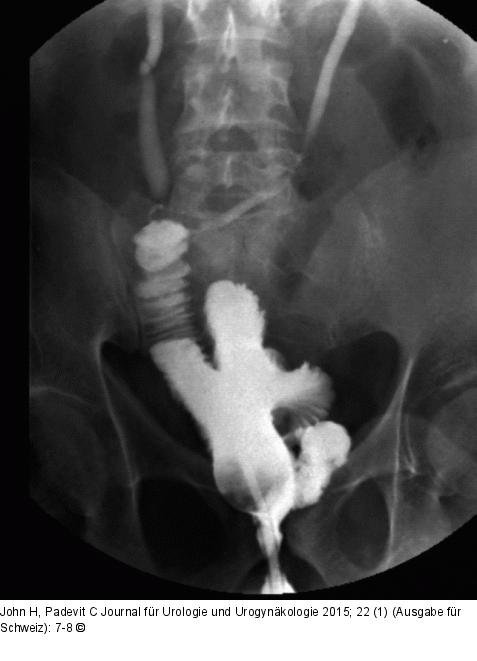

Abbildung 3: Blasentumor Orthotoper Ileum-Pouch. Frühpostoperative Pouchographie vor Katheterentfernung mit korrekt refluxiven Ureteren und dichter Harnröhrenanastomose. |

Abbildung 3: Blasentumor

Orthotoper Ileum-Pouch. Frühpostoperative Pouchographie vor Katheterentfernung mit korrekt refluxiven Ureteren und dichter Harnröhrenanastomose. |